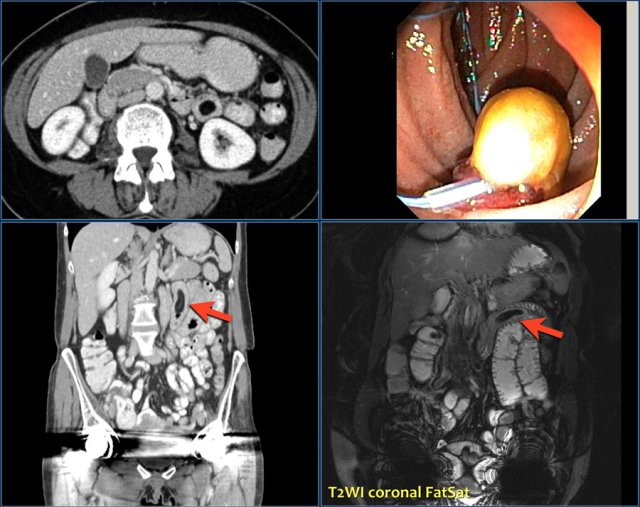

The images show a short obstructing circular mass in the jejunum (yellow arrow) with enlarged lymph node (red arrow).

This proved to be an adenocarcinoma.

Post-contrast T1W-image with fatsat (left) and T2W-image (right) show an obstructing mass in the jejunum with shouldering (arrow).

There is prestenotic dilatation.

Top images show a circular mass in the proximal jejunum with FDG uptake (yellow arrows).

Lower MR-images show the same jejunal mass with shouldered borders and mesenteric lymphadenopathy (red arrows), consistent with adenocarcinoma.